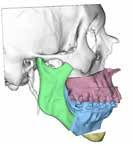

Para completar el estudio, se solicitó una tomografía axial computoriza da craneofacial (TAC) (Figura 1), dónde tras un examen exhaustivo a través de distintos cortes y reconstrucción 3D, evidenciamos una anquilosis de la ATM a la base de cráneo, desapareciendo por completo la anatomía nor mal de la ATM y su relación habitual con las distintas estructuras neurovas culares, así como la gran deformidad esquelética resultante del crecimiento y desarrollo craneofacial anormal.

Una vez los dientes fueron colocados mediante ortodoncia en el lugar estratégico en la arcada, se realizó una planificación quirúrgica 3D de los movimientos quirúrgicos de los maxilares en colaboración con la empresa americana encargada de la confección de la prótesis. Se diseñaron así unas guías quirúrgicas para la resección del bloque anquilótico, unas guías qui rúrgicas para la realización de la mentoplastia y el diseño de la prótesis individualizada y personalizada (Figura 2).

Gracias a esta planificación, se logró una mayor precisión en los movi mientos quirúrgicos, una mayor predictibilidad y reproducción, una dismi nución de los riesgos quirúrgicos por mediciones de estructuras anatómicas concretas (como la arteria carótida interna, el nervio facial, el nervio man dibular, la arteria maxilar interna…) (Figura 1) y un menor tiempo operato rio, entre otras ventajas.

Figura 1. Diagnóstico prequirúrgico del bloque anquilótico. Imágenes TAC en 3D, corte axial y corte sagital..

Figura 2.

Planificación quirúrgica 3D.

A) Diseño 3D de los movimientos quirúrgicos y de las osteotomías maxilares, mandibulares y de mentón.

B) Diseño 3D de las guías de corte para la resección del bloque anquilótico e impresión 3D de modelo estereolitográfico para uso intraquirúrgico.

C) Diseño 3D prótesis customizada, con segmento condíleo y segmentos de fosa glenoidea, y de los tornillos.